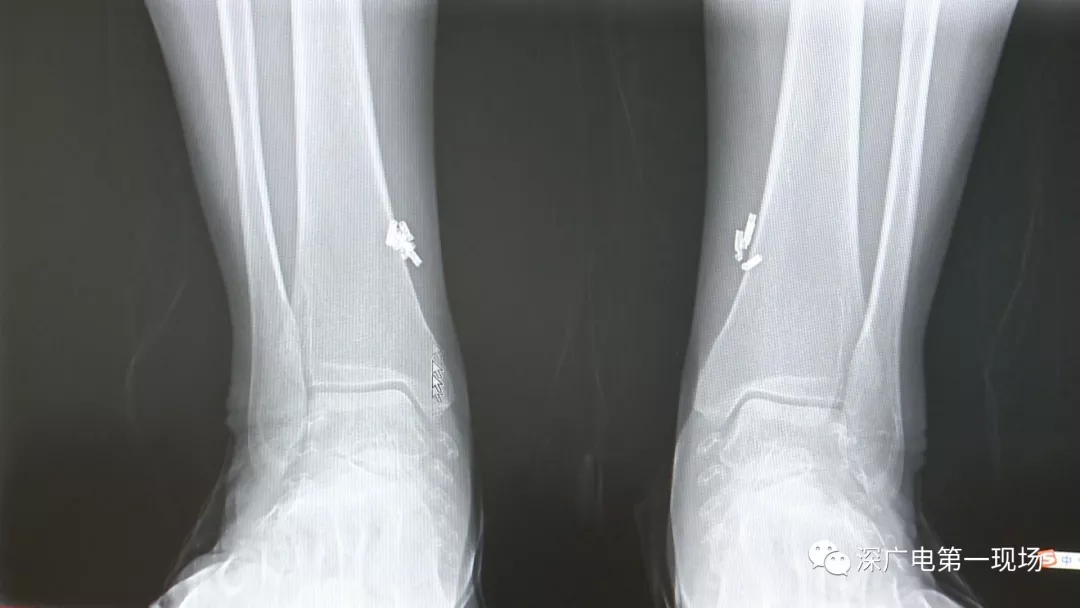

從X光影像圖片中可以看到

患者周身布滿了彈簧圈

深圳大學(xué)總醫(yī)院神經(jīng)外科副主任醫(yī)師陳富勇介紹,當(dāng)時檢查的時候發(fā)現(xiàn),該患者從頭部到腿部,基本上每個地方都有彈簧,很難數(shù)清具體數(shù)目。